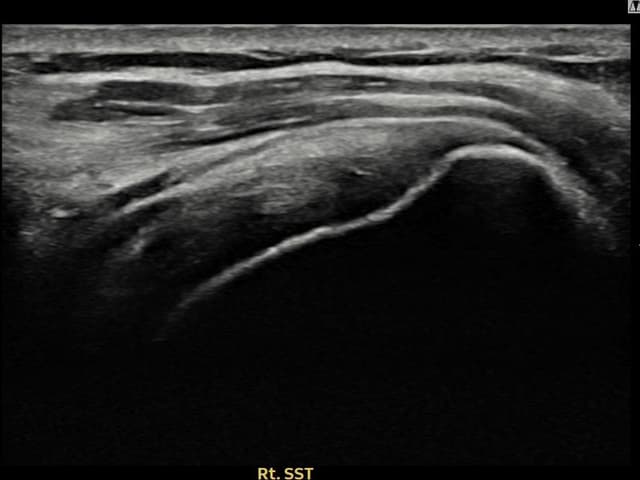

実際の患者様の施術前後の超音波画像。

手術なしで実現できる回復をご確認ください。

[経過期間: 23.08.16~23.10.18]

[縫縮術] 超音波検査にて右 棘上筋腱 関節面側部分断裂(7mm × 3mm (腱厚の約30%欠損))を確認。縫縮術施行後、腱の連続性が回復し、日常生活に復帰されました。